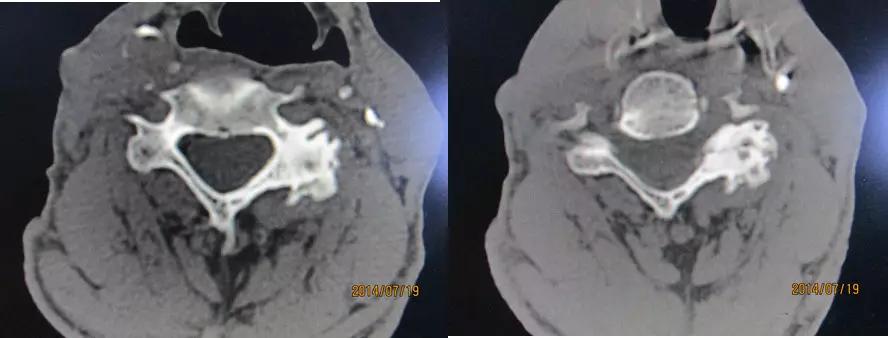

椎间盘突出的CT表现

直接征象:A、椎间盘后缘向椎管内局限性突出,密度与相应椎间盘一致,形态不一。B、突出的椎间盘可有大小、形态不一的钙化,多与椎间盘相连;C、椎管内硬膜外可见髓核游离碎片,密度高于硬膜囊;D、许莫结节表现为椎体上(下)缘边缘清楚的隐窝状压迹,多位于椎体中后1/3交界部,常上下对称出现。其中心密度低,为突出的髓核及软骨板,外周为反应性骨硬化带。

间接征象:A、硬膜外脂肪间隙变窄、移位、或消失。B、硬膜囊前缘或侧方及神经根受压移位。C、周围骨结构改变,突出髓核周围骨质硬化。

椎间盘突出(中央型)

中央型

椎间盘突出右旁中央型

椎间盘突出左旁中央型